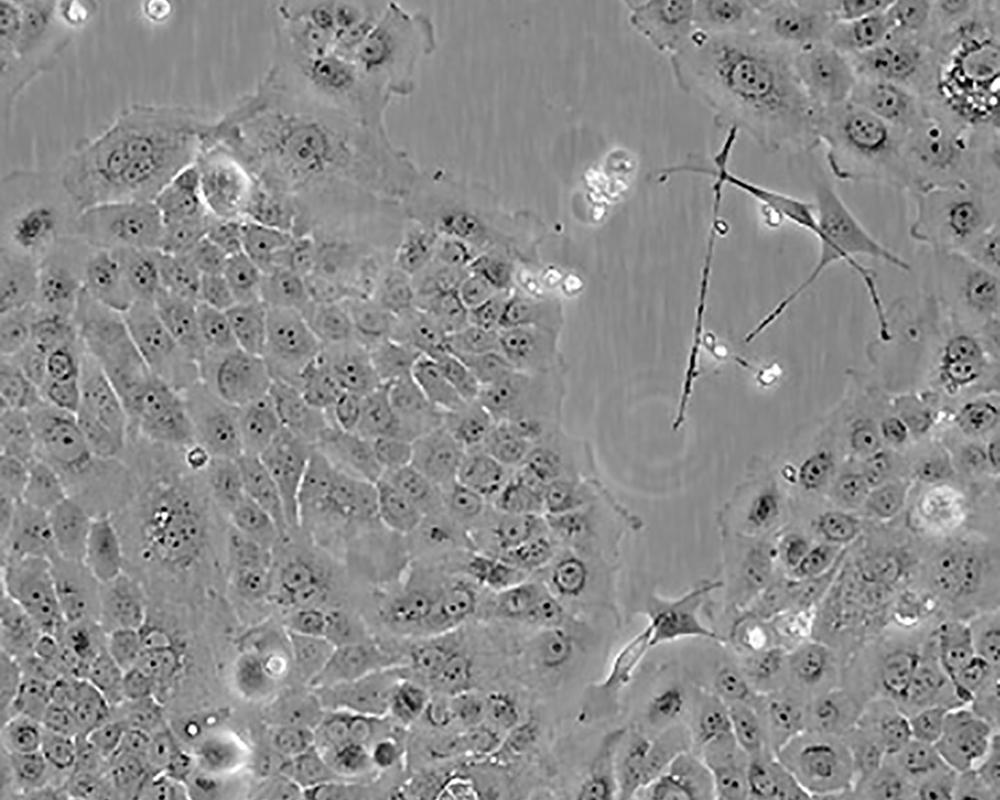

BxPC-3(BxPC3)

產品名稱 BxPC-3(BxPC3)

中文名稱 人原位胰腺腺癌細胞

組織來源 胰腺導管腺癌;女性

生長特性 adherent

形態特征 epithelial